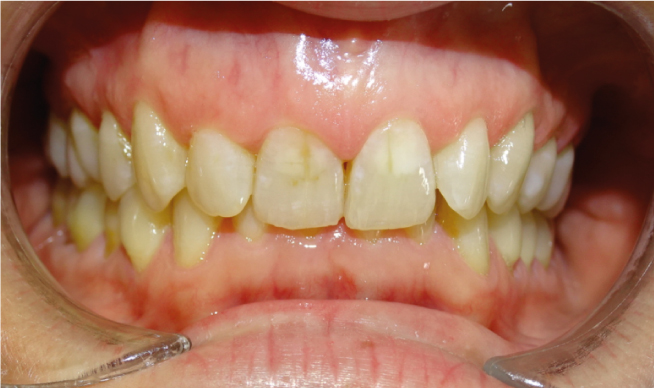

la présence d’une supraclusion, cela signifie que le recouvrement des incisives inférieurs par les incisives supérieures est trop important. Autrement dites, les dents du dessus « cachent » celles du bas, c’est pourquoi on parle aussi de recouvrement dentaire. La supraclusion se manifeste par un recouvrement trop important des incisives inférieurs par les incisives supérieures. Les dents du dessus « cachent »les dents du bas. Ce trouble est fréquent et est aisément traitable grâces aux nouvelles techniques d’orthodontie. Grâce aux nouvelles techniques d’orthodontie, le traitement est facilité́. Il n’est plus nécessaire de porter des « casques » externes et il est très rare d’extraire des dents. Le port de rackets (les « bagues ») permet de résoudre le problème chez l’enfant et l’adulte.